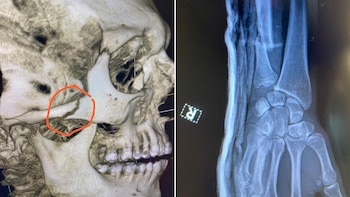

Dado el aspecto escalofriante y el llamativo sonido provocado se interpreta que allí sufrió la primera del dúo de fracturas que lo acompañó en la pelea. Eso se describe en la radiografía de cráneo practicada después de la batalla, donde se llega a observar la rotura del hueso ubicado en la mejilla derecha de su rostro. Este análisis fue subido en sus redes sociales. El golpe generó un torrente de sangre divisible en el final de las acciones en Nevada, aunque lo desestimó tras declarar que solo se trataba de un “rasguño” en charla con el comentarista de UFC, Joe Rogan.

“Justo al empezar el segundo asalto, me miro el brazo porque no responde como yo quiero, y entonces, él asesta un par de patadas más y creo que eso lo rompe. Definitivamente lo sentí en el segundo round. Me dije: ‘Aquí pasa algo’”, remarcó el deportista de 33 años. Por si las palabras no alcanzan para describir el cuadro, el peleador publicó una impresión de los estudios en su cuenta personal de Instagram para detallar la gravedad.

De igual forma, en su permanencia dentro de la jaula disimuló estas molestias de gran manera y estuvo cerca de dar por concluido el combate a su favor, pero no llegó a completar la sumisión contra el estadounidense de 28 años en el cierre del segundo acto. “Yo no podía sentir mi mano derecha, y luego no fue hasta la tercera ronda, lo dejé caer y traté de acabar con él, yo estaba siguiendo con golpes, y fue un golpe y yo estaba como: ‘Voy a lanzar mi mano derecha de todos modos’. Lancé el derecho y sentí que se me iba completamente de sitio. Todo mi brazo derecho se quedó muerto. No quería ganar así”.